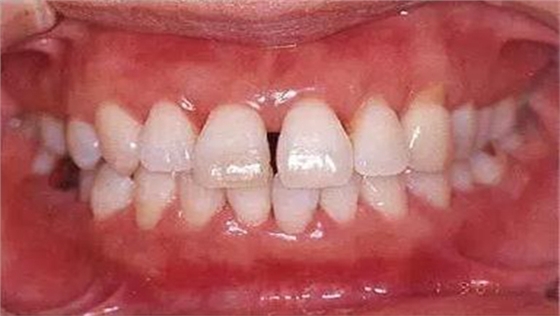

●33歲男性 侵襲性牙周炎廣泛型口腔內(nèi)照片

33歲男性,吸煙(1天10根,12年吸煙史)。菌斑控制狀況不好,牙周探診全頜牙周袋深5~10mm之外,全頜性牙周袋出血,部分牙周袋有排膿現(xiàn)象。X片可觀察到全頜性重度骨吸收。通過(guò)以上檢查可診斷出該患者為侵襲性牙周炎廣泛型。視診可知牙齦雖然有炎癥,但沒(méi)有出現(xiàn)嚴(yán)重浮腫,沒(méi)有大量牙結(jié)石沉積。